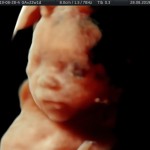

Modalidad de imagen ecográfica que permite evaluar, medir y capturar estructuras fetales superficiales e internas en 3 dimensiones (3D) y también en movimiento y en tiempo real (4D) con programas de realismo aumentado (HD LIVE) e imágenes tomografías fetales (TUI) mejorando significativamente la precisión en las mediciones fetales y la documentaciones de estructuras anatómicas.

Esta tecnología se puede utilizar desde la 6ta a la 40ma semana de embarazo.